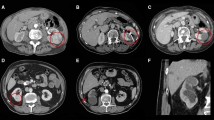

Technical success was achieved for 28 of 29 patients, 29 of 30 tumors (97%); stratified by stage, 22 T1a (96%) and 7 T1b (100%) were successful. The single primary failure was an oval-shaped T1a (2.9 cm) chromophobe subtype RCC, Fuhrman grade not specified, with a RENAL nephrometry score of 4p. Single corticomedullary phase, CECT, and pre- and peri-procedural US did not adequately characterize the true shape of the tumor and endophytic extent of the tumor. On immediate post-procedure axial CECT reviewed at the CT scanner following the procedure, the zone of ablation appeared to cover the index tumor including an adequate margin. Upon review of the coronal and sagittal reformatted images, available after the patient was awakened and transported to the post-anesthesia care unit, unabated tumor could be seen extending to the renal sinus and this was confirmed at MRI on six-month follow-up (Fig. 1). This patient was successfully retreated with salvage MW ablation conferring a primary effectiveness of 96% and secondary effectiveness of 100% for T1a RCC and a primary effectiveness of 100% for T1b RCC.

Percutaneous microwave ablation of a 2.9 cm chromophobe RCC partially endophytic T1a chromophobe RCC (arrow) on axial CECT (A). One microwave antenna (arrowhead) was placed into the mass, tangential to the renal sinus, with US guidance and position confirmed with CT (B). Lobular low-attenuation extending from the index ablation to the renal sinus (curved arrow) on the sagittal CECT (C) was discovered in retrospect, following the procedure after the patient was awakened. This primary failure (curved arrow) was confirmed at 6-month follow-up MRI (D)

Our results are additive and further validate prior high treatment success of MW ablation for biopsy-proven T1a RCC with low and moderate tumor complexity [13]. The lone treatment failure, a T1a chromophobe RCC with a RENAL nephrometry score of 4p, was the result of suboptimal pre-procedure imaging that failed to characterize the endophytic extent of the tumor. Based upon pre-procedure imaging findings, a tangential (to renal sinus), rather than perpendicular, approach was used for antenna placement. A single MW antenna was not able to overcome the robust perfusion-mediated tissue cooling intrinsic to the kidney with this antenna position (Fig. 1)

With a LTP rate of 0% at a mean follow-up of 8.6 months for T1b RCC, our results compare favorably with prior reported experiences. In a subset analysis of biopsy-proven T1b RCC, Yu et al. had a 50% rate of treatment failure (87% primary efficacy, 43% LTP) [12]. There are several potential explanations for our improved results. In our study, the endpoint of MW ablation sessions was based upon imaging findings rather than temperature feedback from a thermocouple or a strict power/time prescription. When gas covered the index tumor and a narrow margin, the ablation session was considered complete (Fig. 2). Staged ablations, repeat ablation sessions, and overlapping ablations used to treat T1b tumors in previous studies were not performed in our study. We used a 2.45 GHz MW device with up to three antennas whose output was synchronized to preclude destructive interference. The resulting large, confluent, spherical ablations were able to cover T1b tumors in a single treatment session without the need for overlapping ablations (Fig. 3). General anesthesia was used for every case in our study. The collaboration with anesthesiology allows the operators full attention to be directed toward the index tumor, placement of applicators, and monitoring the zone of ablation. Our anesthesia colleagues managed patient factors unrelated to the ablation including hemodynamic status and airway and also performed adjunctive maneuvers, such as Valsalva and apnea, which improve index tumor conspicuity and tumor targeting. Our results suggest that MW ablation may have a greater role in the management of T1b RCC than had been previously supported by the literature [1].

Percutaneous microwave ablation of a 4.8 cm pRCC endophytic T1b papillary RCC (arrow) on axial axial CECT (A). Three microwave antennas (arrowhead) were placed into the mass with US guidance and position confirmed with CT (B). Immediate post-procedure axial CECT (C) demonstrates complete tumor ablation including a narrow margin and no complication (arrow). There is no evidence of LTP at 12-month follow-up MRI (D). Notice the intrinsic T1W signal of the index ablation (arrows) at MRI (D) can be effectively subtracted (E) to improve diagnostic confidence